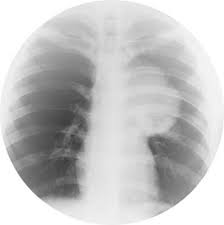

The second is the treatment by radiation. This treatment uses x-rays of high energy to destroy cancer cells. The radiation source can be internal or external. If the radiation from a machine, if it is known as external radiotherapy. If Radioisotopes produce radiation are thin plastic tubes in the lungs, then it is also the internal radiation therapy.